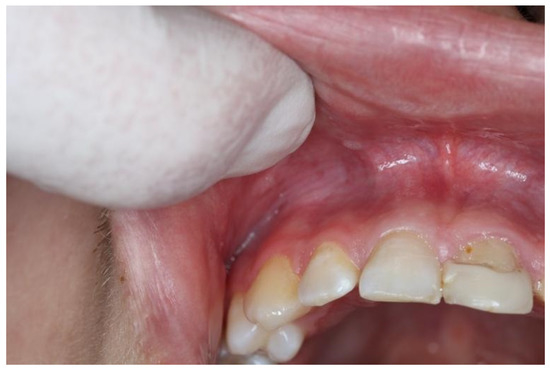

| Snus | 5–10 | 2–5 | White, leathery lesion (Figure 1) | Above tooth nr. 13 to tooth nr. 22 |